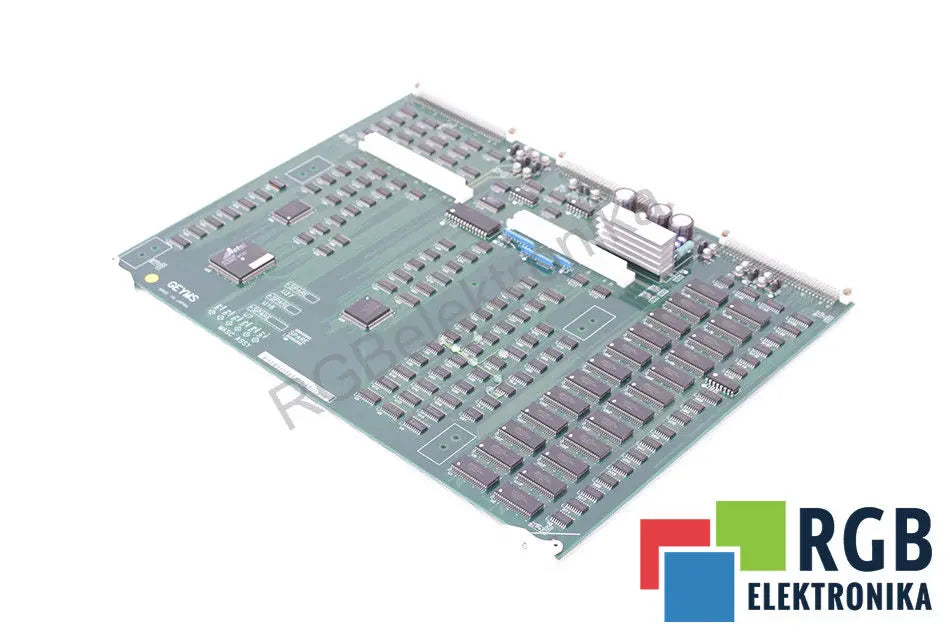

GEYMS 2123317 MASC ASSY FOR LOGIQ 400 MD MEDICAL ULTRASOUND GE YOKOGAWA ID20607

Sale price$ 1,522.73

Regular price$ 1,856.99

GEYMS 2123325-02 REV. 01 FOR LOGIQ 400 MD MEDICAL ULTRASOUND GE YOKOGAWA ID20604

Sale price$ 568.25

Regular price$ 692.99

GEYMS 2150016 REV. 00 FOR LOGIQ 400 MD MEDICAL ULTRASOUND GE YOKOGAWA ID20605

Sale price$ 368.17

Regular price$ 448.99

GEYMS DGPCIO Assembly Board 2349224 2349225 for GE Logiq 7/9 Ultrasound

Sale price$ 557.59

Regular price$ 679.99